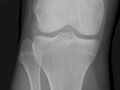

Extremity X-Ray

An extremity X-ray is a picture of your hand, wrist, arm, foot, ankle, knee, hip, or leg. It is done to see whether a bone has been fractured or a joint dislocated. It is also used to check for an injury or damage from conditions such as an infection, arthritis, bone growths (tumors), or other bone diseases, such as osteoporosis.